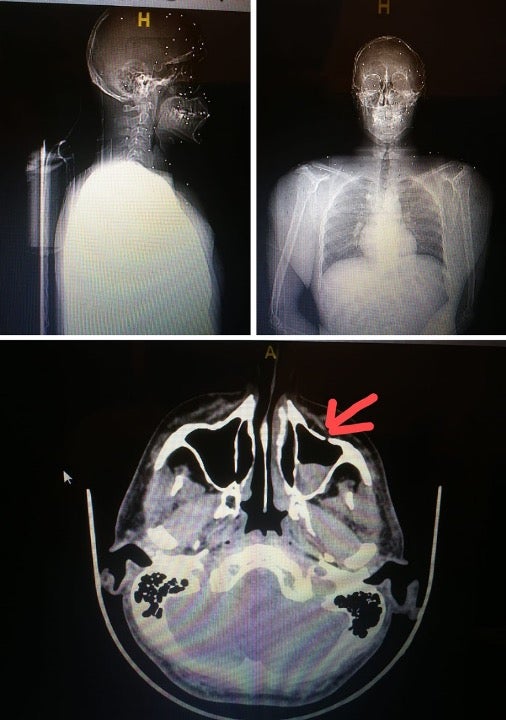

Dozens of pellets wounded this protester, puncturing their scalp and embedding under their sinus and in their eye.

© 2020 Private